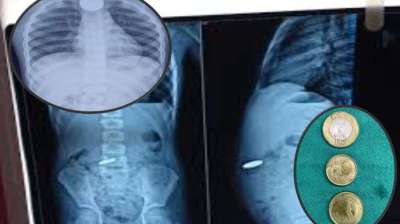

खेलते-खेलते बच्चे ने निगल लिए सिक्के, खाने की नली में फंसे; डॉक्टरों की टीम ने ऐसे बचाई जान

दिल्ली : दिल्ली के एक सरकारी अस्पताल के डॉक्टरों ने 12 वर्षीय बच्चे की जान बचाई है। बच्चे ने पांच और दस रुपये के तीन सिक्के निगल लिए थे। सिक्के...